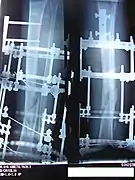

X-Ray of the fracture site immediately following the application of the Ilizarov method

X-Ray of the fracture site, part 1 (two months following fracture)

X-Ray of the fracture site, part 2 (two months following fracture)

X-Ray of the fracture site (three months following fracture). Note formation of bone callus around fracture site.

X-Ray of the fracture site, part 2 (three months following fracture). Note formation of bone callus around fracture site.

X-Ray of the fracture site, part 2 (four months following fracture)